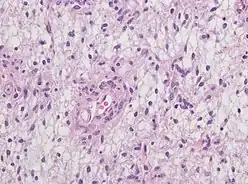

Neuropathology

Neuropathology is a specialty within the study of pathology focused on the disease of the brain, spinal cord, and neural tissue.[33] This includes the central nervous system and the peripheral nervous system. Tissue analysis comes from either surgical biopsies or post mortem autopsies. Common tissue samples include muscle fibers and nervous tissue.[34] Common applications of neuropathology include studying samples of tissue in patients who have Parkinson's disease, Alzheimer's disease, dementia, Huntington's disease, amyotrophic lateral sclerosis, mitochondria disease, and any disorder that has neural deterioration in the brain or spinal cord.[35][36]